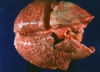

Q

This is the stomach of a horse. What lesion is shown here?

A

equine gastric ulceration